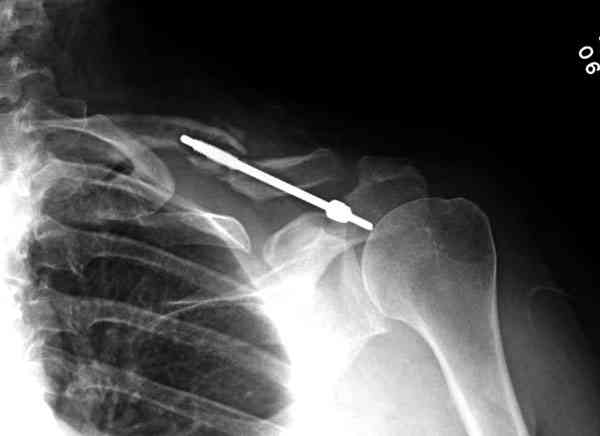

iГГШ> выполнения новокаиновой блокады дежурной бригадой выполнена закрытая

ГГШ> репозиция, наложены кольца Дельбе. Результаты репозиции показаны на

ГГШ> Результат стационарного лечения приведен на рентгенограмме (Xray_3).

Это картинка то есть через неделю после травмы, при выписке? Более чем приемлемо.